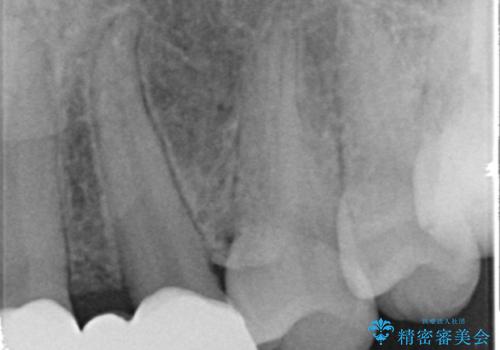

- 生まれつき上の側切歯と犬歯が逆に生えていることを主訴に来院された患者様です。

他院で矯正を行っていたそうですが、なかなか終わらないため途中で治療をやめてしまったとのことでした。

矯正以外の治療法で早く治したいとのご希望により、上顎両側犬歯を抜去しオールセラミックのブリッジによる補綴治療を行いました。

- ¥660,000 (仮歯×6本、クラウン×6本)費用は治療当時の料金となります